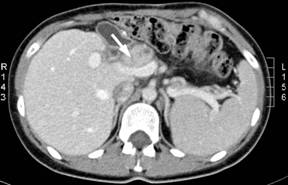

Based on this, 23 months after initial operation of the patient two recurrent metastatic fibrolamellar hepatocellular tumors were for the first time found and excised at the Department of Hepatobiliary Surgery and Liver Transplantation, Marie Curie Hospital in Szczecin, Poland where the surgical treatment was continued. The recurrences were located in the lymph nodes adjacent to the pancreatic head (6x5 cm) and in the left retroperitoneal space (7x6 cm). Eighteen months later, a tumor (3x3.5 cm) located within the hepatoduodenal ligament and compressing the portal vein was detected (Figure 1). The treatment consisted of a local tumor excision combined with a Roux-en-Y hepaticojejunostomy, as the transection of the common bile duct was necessary for complete tumor removal. The pathologic examination confirmed the diagnosis of metastatic fibrolamellar hepatocellular carcinoma. Sixteen months after the third operation, another metastatic fibrolamellar hepatocellular tumor (5x4 cm) was found (Figure 2) and excised from the space located between the lesser curvature of the stomach and the left diaphragm. This was followed by a CT scan detecting an isolated left intrathoracic nodule 13 months after the fourth operation. The tumor measured about 4 cm in diameter and was located directly above the diaphragm and very close to the caval vein (Figure 3). Resection of this nodule was done at 72 months of follow-up using a left posterior thoracotomy and the pathologic diagnosis of metastatic fibrolamellar hepatocellular carcinoma was confirmed.

Figure 1. Abdominal CT scan performed at 41 months of follow-up showing lymph node recurrence within the hepatoduodenal ligament (arrow) which is compressing the portal vein. |